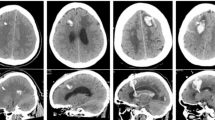

A total of 10 catheter implantations were performed in human cadaver specimens. All catheters were implanted in the frontal horns of lateral ventricles in the first attempt leading to a 100% first pass success rate. The 3D Euclidean error (3D distance) between the software-planned and the frame-targeted coordinates was 1.8 ± 0.6 mm (n = 10, Fig. 3J). We also measured the deviation of the catheter from its trajectory in the XY plane of the target and referred to it as the trajectory error. The trajectory error was found to be 1.9 ± 0.8 mm (n = 10, Fig. 3J). The distance of the margin of catheter tip from the FOM was found to be 3.9 ± 1.6 mm (n = 10). The average time taken for key placement, surgical planning (including fiducial registration), and EVD implantation was 1.6 ± 0.4 min (n = 4), 9.4 ± 3.5 min (n = 10), and 14.7 ± 2.6 min (n = 8) min, respectively (Fig. 3K). Two observations for implantation time were excluded as they employed a pre-existing burr hole. The total time for the procedure excluding the CT scan was 26.5 ± 3.1 min per implant (n = 8, Fig. 3K). Figure 4 shows the targeting accuracy assessment of a representative experiment by superimposing the planned trajectory on the actual trajectory using COMPASS surgical planning software (COMPASS International Innovations, Rochester, MN). The entire procedure was completed on the CT scanner table without transporting the specimen.

CT images showing robust targeting accuracy in a representative pre-clinical experiment (COMPASS software). The actual location of catheter tip (red circle) is seen to be overlying the planned location (blue dot). The bottom right panel shows the actual catheter trajectory (white glow) with superimposed planned trajectory (red line). Cerebral vasculature was avoided while placing the catheter.

The catheter tip was located within ipsilateral frontal horn in all implantations and thus judged Grade I (optimal/adequate) as per Kakarla et al.'s clinical grading system1 (supplementary Table S1). For 9 implantations, the catheter tip was located within 5 mm of ipsilateral FOM and judged as ideal based on Fargen et al.’s4 grading system (supplementary Table S2). For one implantation, the tip was placed 8 mm from the FOM in the ipsilateral lateral ventricle and judged as acceptable. For experiments emulating surgical planning with CTA, a thorough visual inspection of the post-procedure CT images revealed no direct contact of the catheter with visible vessels (n = 5, see Fig. 4, bottom right panel for representative image).